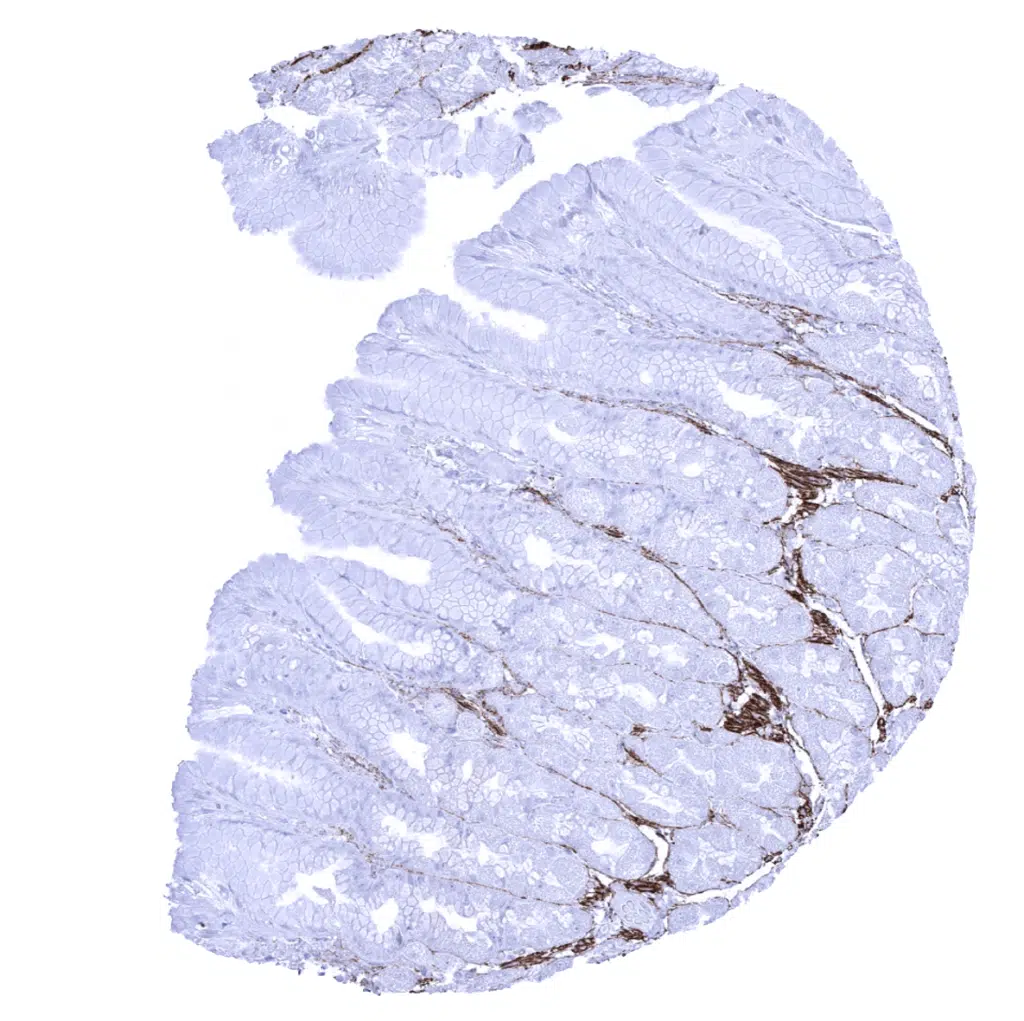

Elastin antibody [MSVA-648R] HistoMAX

Colon descendens, mucosa – Elastin fibres predominate in the lamina propria, around smooth muscle cells of the muscularis mucosae, and in blood vessels.

Colon descendens, muscular wall – Smooth muscle cells are surrounded of by elastin fibres.